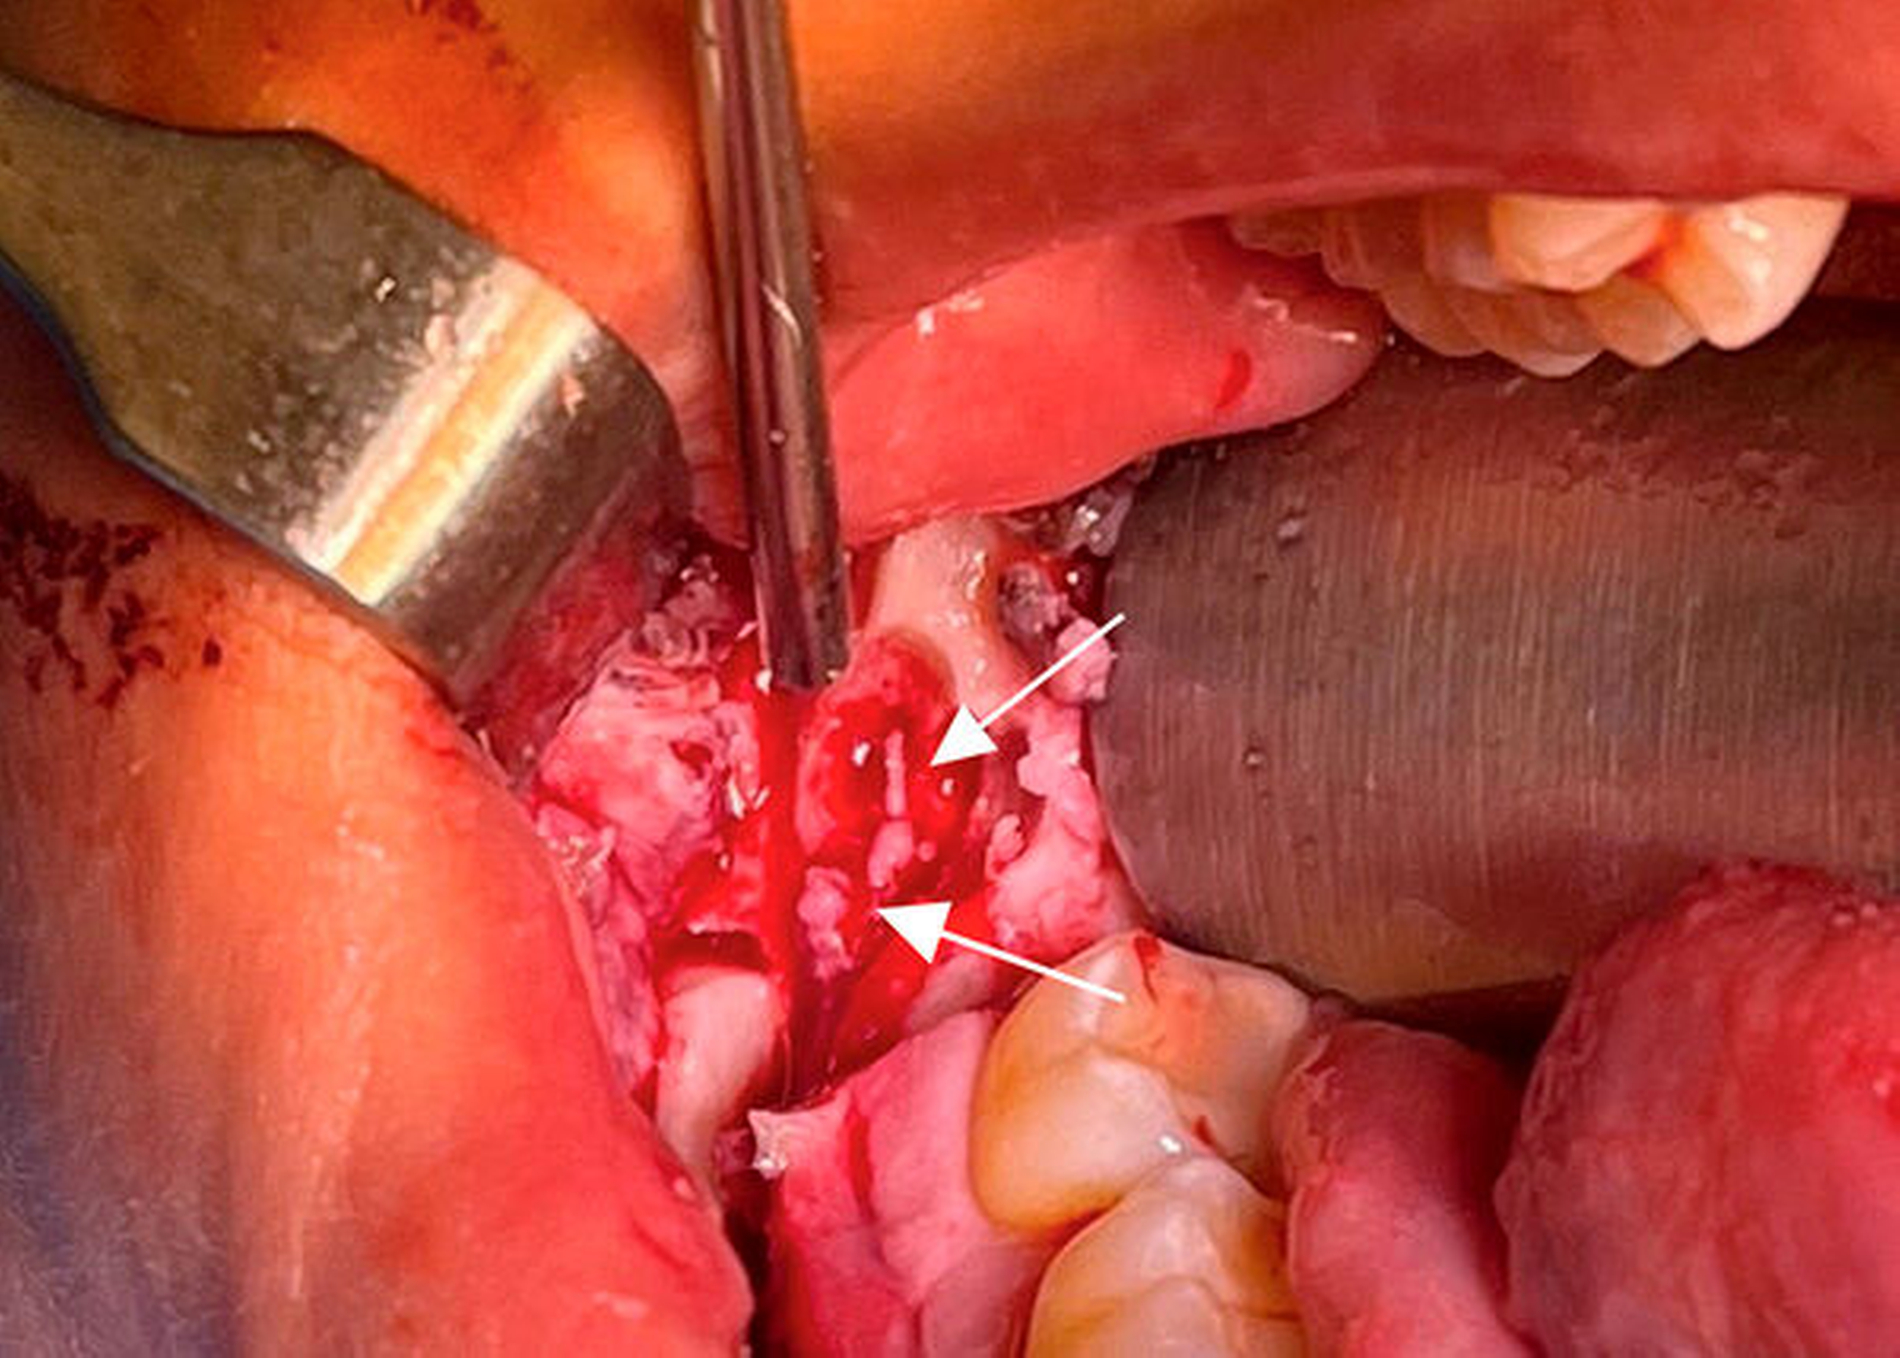

Nach krestaler Schnittführung erfolgte die Darstellung des vestibulären Unterkiefers. Beginnend am Foramen mentale wurde mittels Piezochirurgie eine schonende Osteotomie des Knochens entlang des Nervverlaufs durchgeführt. Nach Darstellung des retromolaren Anteils des Nervkanals zeigten sich eine deutliche Kontinuitätsunterbrechung des Nervus alveolaris inferior ebenso wie eine neurinomverdächtige Struktur, die im Rahmen der Operation entfernt werden konnte (Abbildung 3). Nach Entnahme des Nervus-suralis-Interponats aus der rechten Knöchelregion (Abbildung 4) wurde der residuale Nervus alveolaris inferior angefrischt und das Interponat mittels intrafaszialer Nähte (Größe 10-0) mit den beiden Enden des Nervus alveolaris inferior anastomisiert (Abbildung 5). Anschließend wurde der Nerv mit einer Platelet-rich-fibrin (PRF-)Membran abgedeckt und der entstandene Defekt mit dem entnommenen Knochendeckel verschlossen (Abbildung 6).